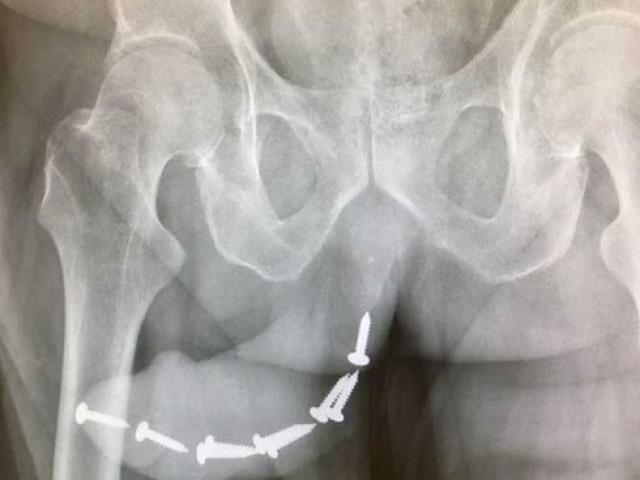

Tại bệnh viện Nam học và Hiếm muộn Hà Nội, anh được các bác sĩ chẩn đoạn bị rối loạn cương dương mà hệ quả của thời gian dài quan hệ tình dục quá độ.

Đặc biệt có trường hợp còn bị teo bé dương vật (đây chính là kết quả của ba quá trình: giảm androgens làm teo cấu trúc xoang hang, giảm chất đàn hồi mô như prostaglandin E1, E3 và Nitric Oxide và co thắt động mạch mạn tính)…